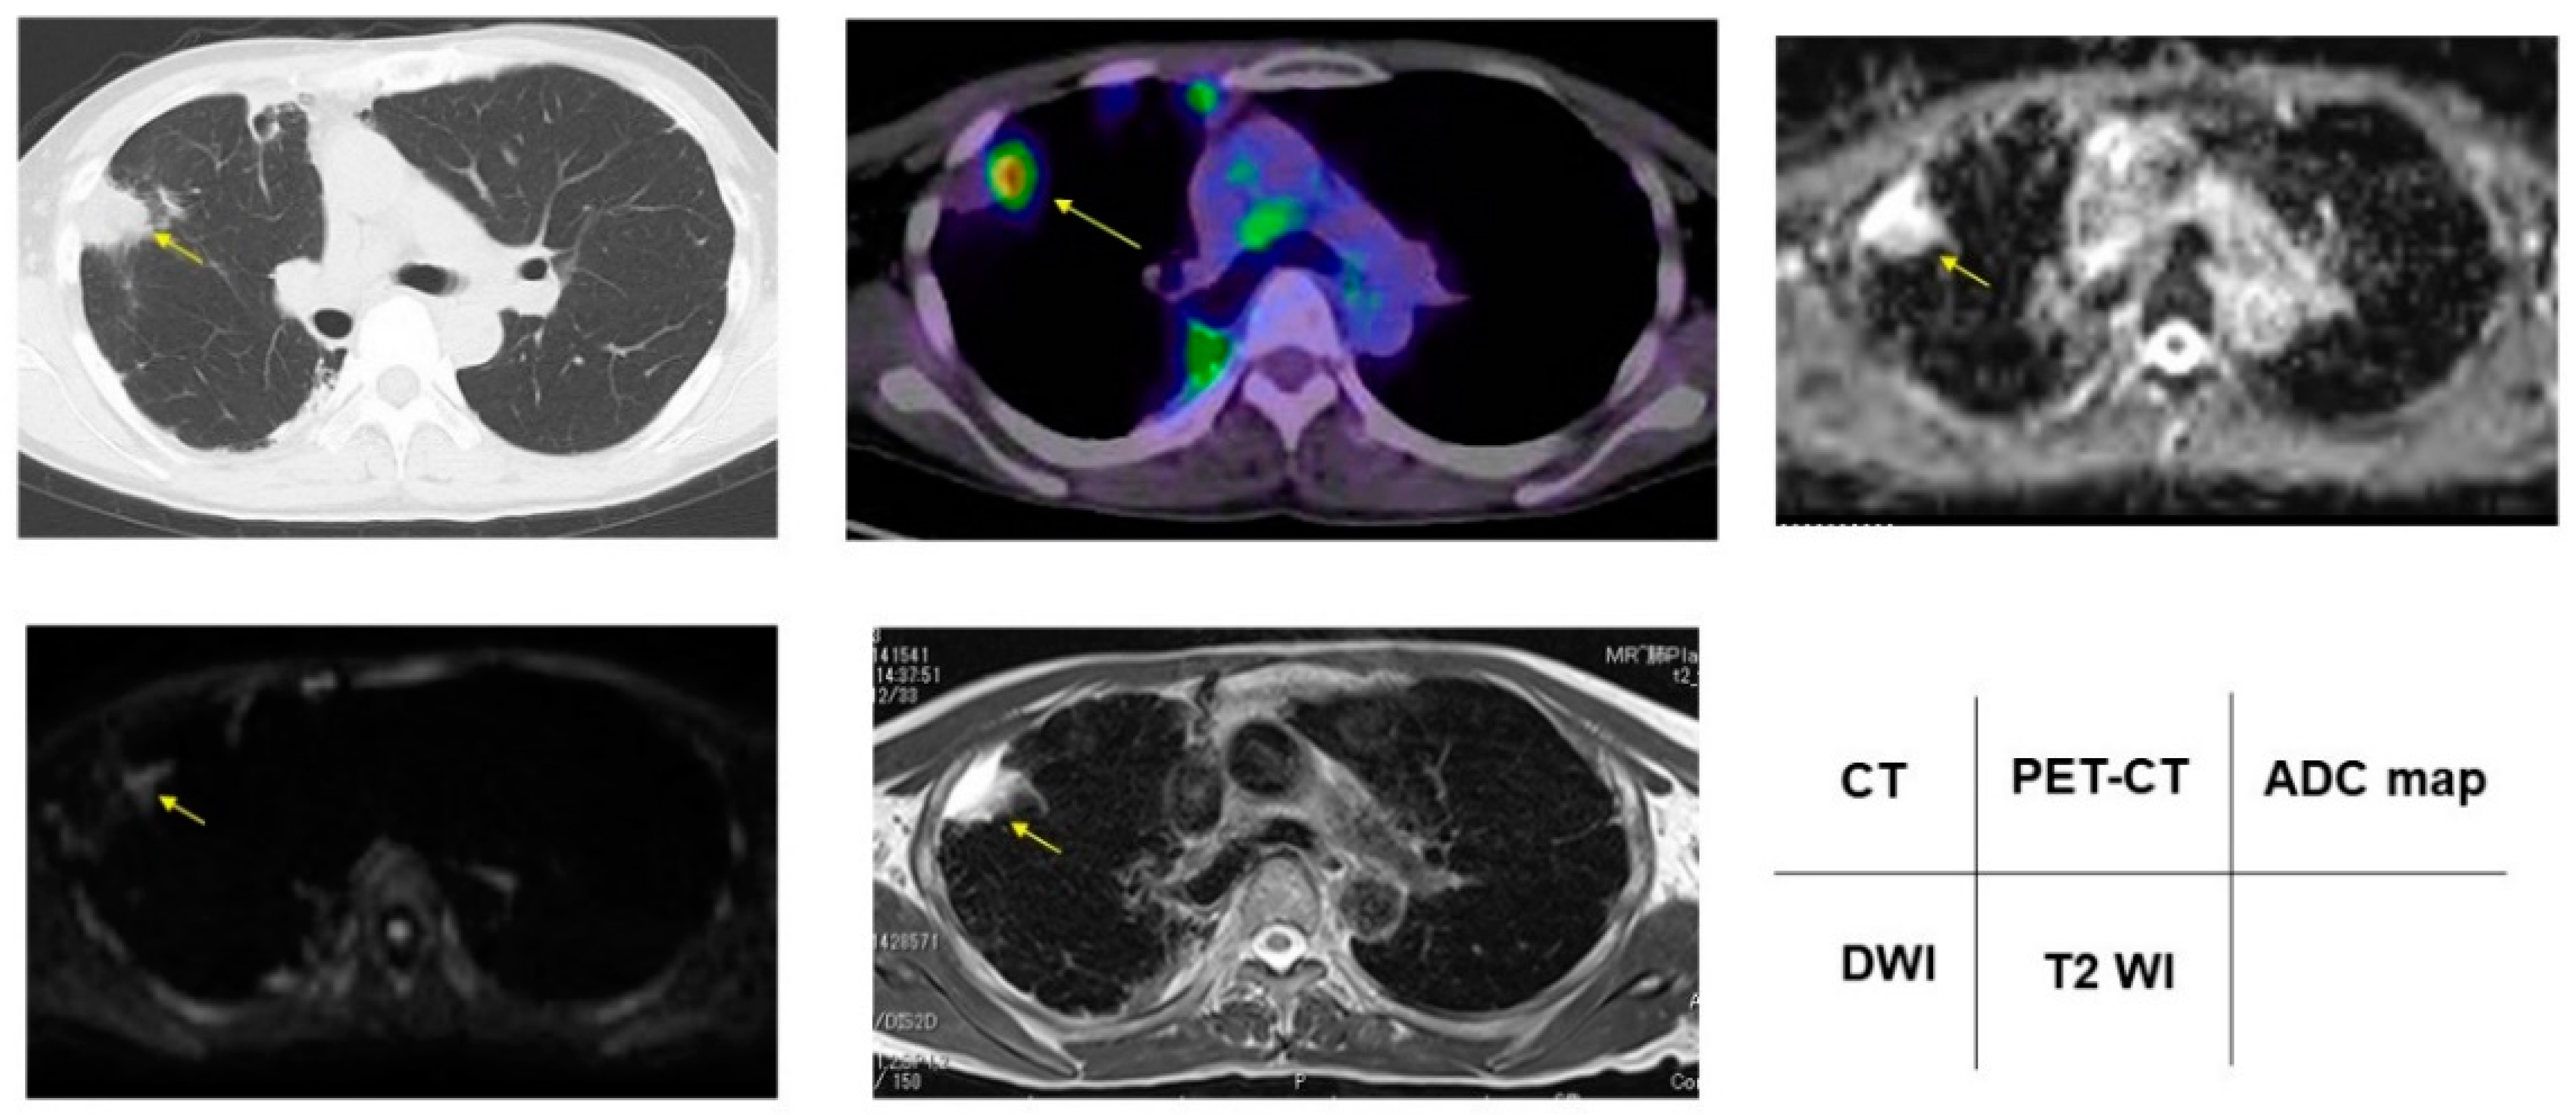

3.2. Radiologic Presentations of CT, FDG-PET/CT, DDS of DWI, ADC Map and T2WI in PNMs